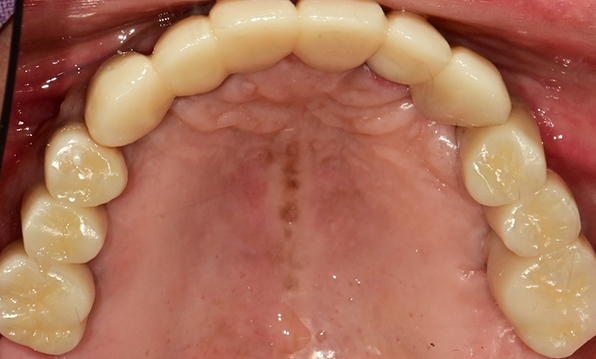

잇몸뼈가 얇은 상태

-

잇몸뼈 충분히 이식 후 임플란트 식립

성공을 위한 노하우, 잇몸뼈 재건 기술

전체 임플란트를 해야하는 환자들은

대부분 고령의 환자들로 오랜 틀니 사용

또는 노화로 인해 치조골이

거의 남아있지 않는 경우가 많습니다.

이 때, 치조골 이식을 병행하여 잇몸뼈 재건 후 안정적인 임플란트 식립을 하고 있습니다.

치료기간 : 2021.04.12~2021.09.15